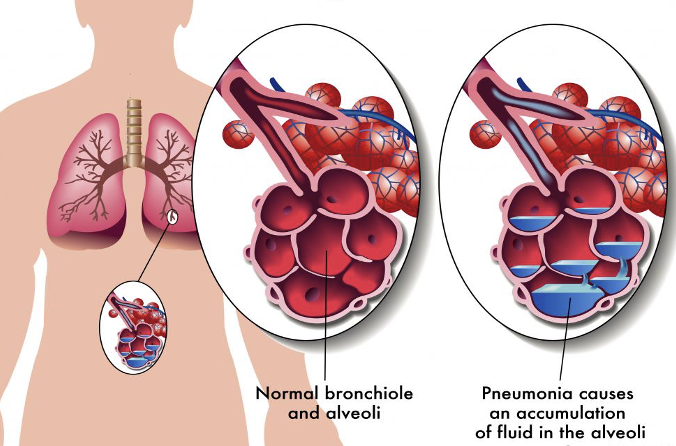

- Bacteria enter the lungs (from the throat or nose, airborne droplets, or blood).

- Bacteria may invade the spaces between cells and between alveoli.

- The macrophages and neutrophils inactivate the bacteria. The neutrophils also release cytokines.

- This causes general activation of the immune system.

- Leading to fever, chills, and fatigue.

- The neutrophils, bacteria, and fluid fill the alveoli.

- Resulting in the consolidation seen on chest X-ray.